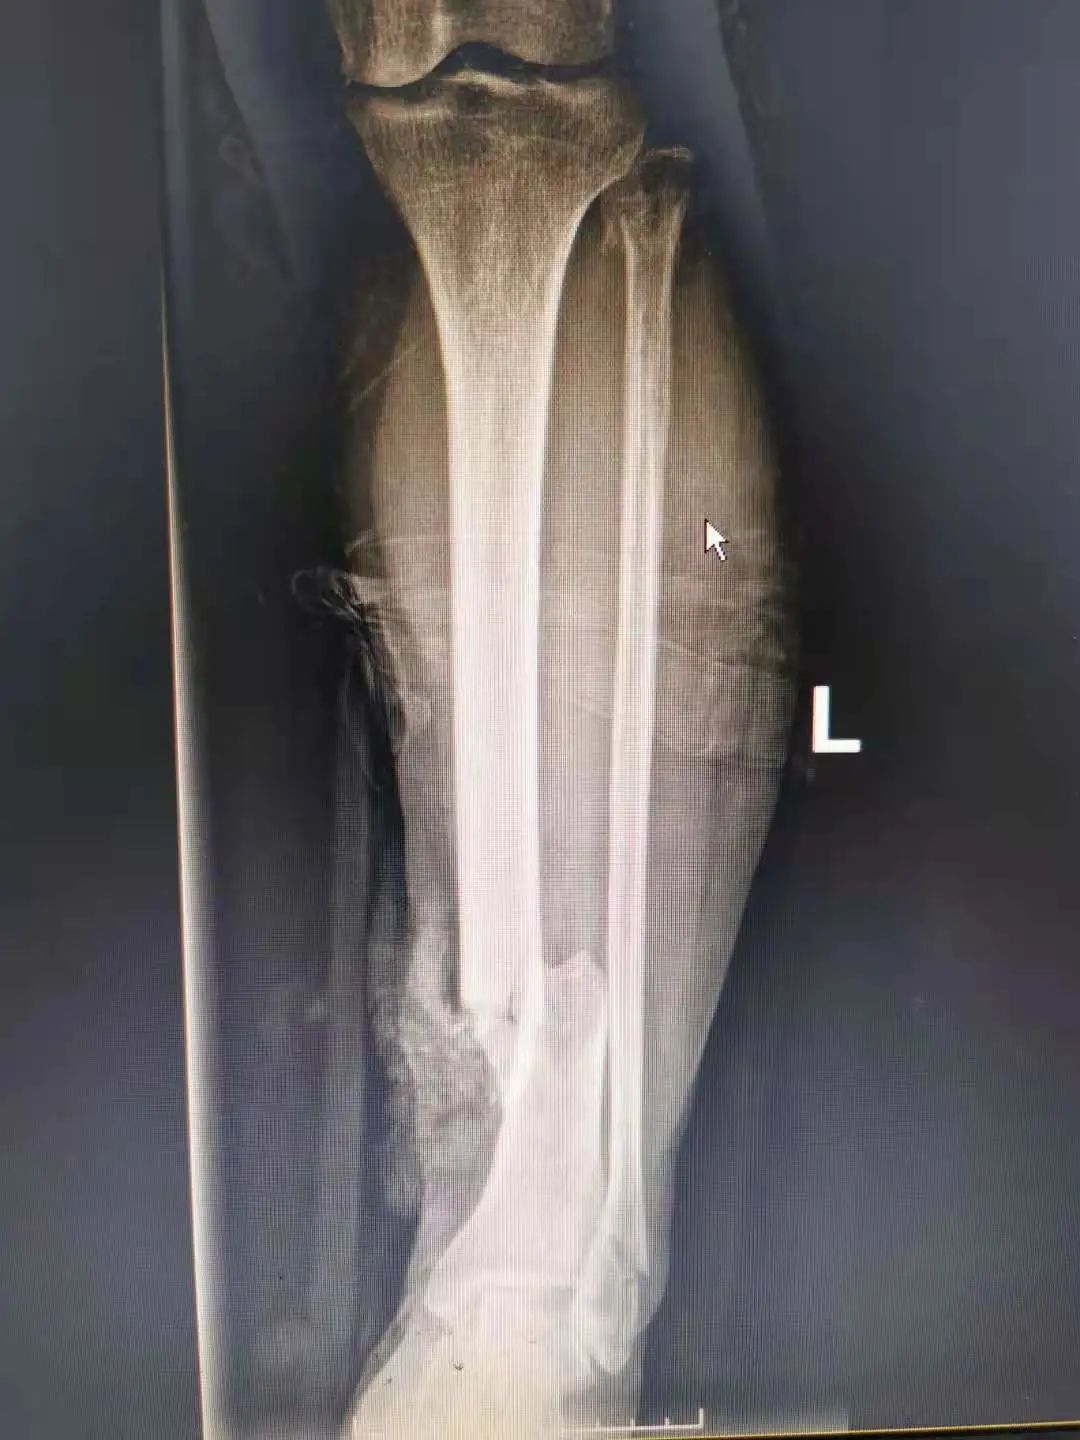

患者吕女士,66岁,因车祸受伤被送到我院急诊科,入院时左小腿上有一个镰刀型的伤口,长约15厘米,血肉模糊,经检查发现患者小腿前群肌肉挫裂严重,左胫骨开放粉碎骨折,骨质外露,创面及骨髓腔内大量泥土、布丝等污染物,急诊科完善相关检查后将患者送至骨科一区进行进一步治

疗。

术前